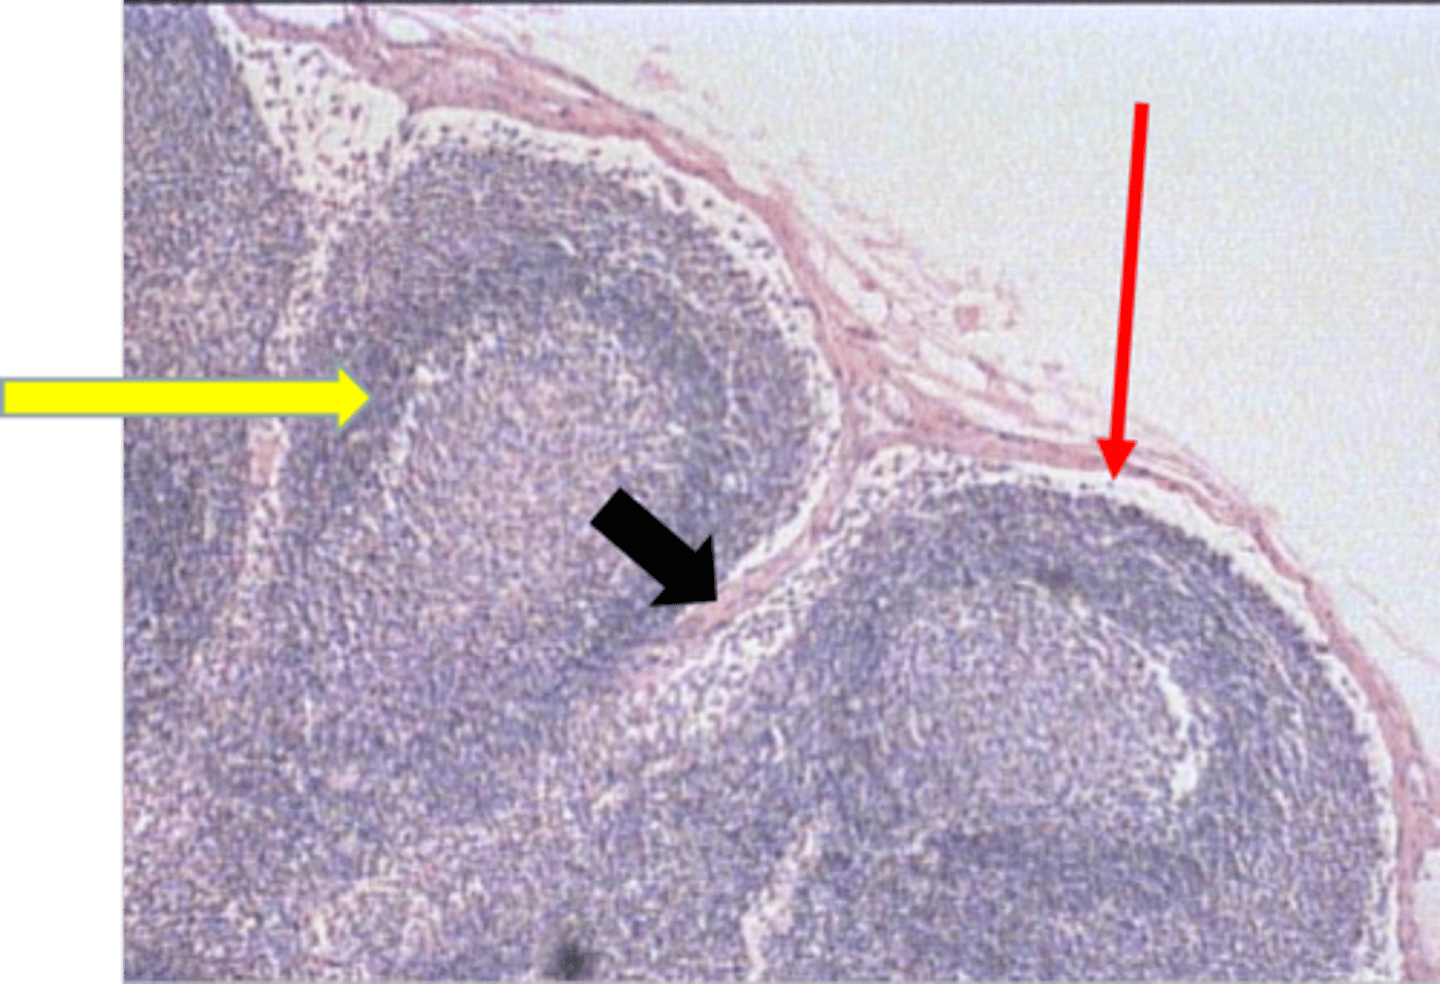

sinusoidal capillary

blue arrow sinusoidal capillary

splenic cord

yellow arrow splenic cord